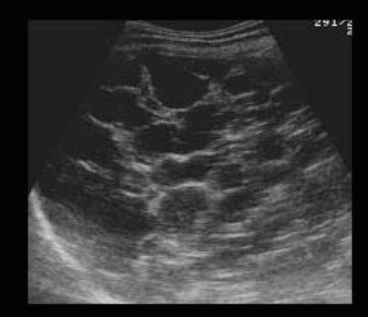

US finding

- 원형으로 경계가 분명한 단순낭종이다.

- 큰 낭종 안에 작은 낭종이 존재(daughter cyst)

- 낭종벽내 석회화가 관찰된다 (cyst wall calcification)

- 백합모양(water-lily sign)

daughter cyst and water-lily sign ②아메바성 간농양 (amoebic abscess)